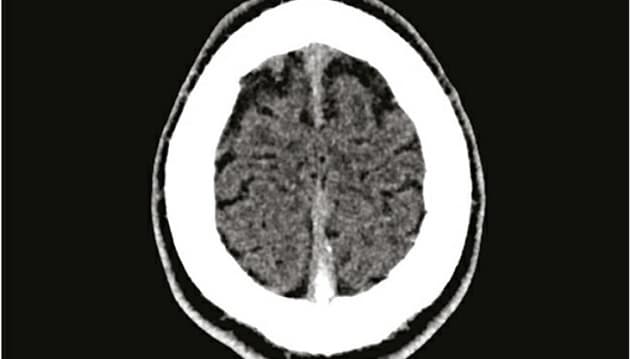

Patientens trombose var så stor, at den kunne ses på et CT-billede af cerebrum uden kontraststof. Ugeskr Læger 2021;183:V06210511